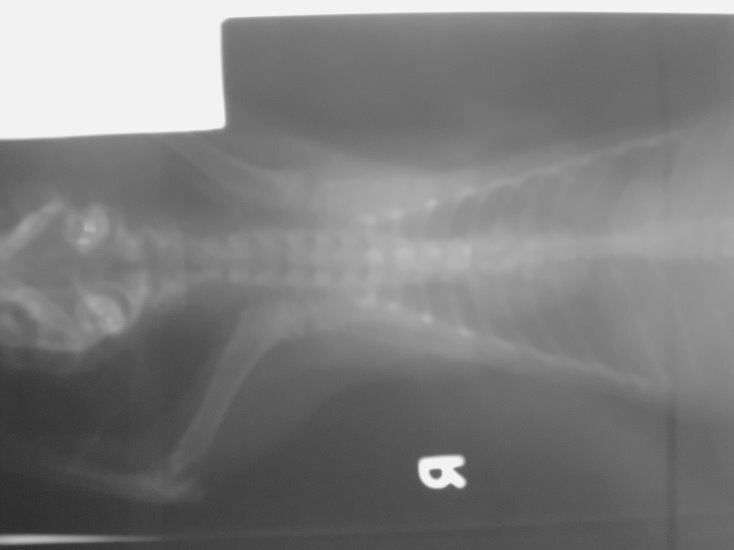

- 編號: 731

主題: 疑似受外力撞擊且有鼻氣管炎的親人小虎斑 申請者姓名: 陳露露 花色: 申請日期: 2012-08-07 03:32:03 申請者部落格: 申請者臉書網址: 所在縣市/合作醫院: 高雄市/樂生動物醫院 治療費用: 4200元 需求人數: 5人 已結案 (2012-12-08 19:10:30) 報名人員: Chinia(已付款)、吳家儀(已付款)、連珮宇(已付款)、龍豪(已付款)、龍豪(已付款)、 候補人員: 小舟、 動物病情說明: 7月23日的深夜,

經過醫生仔細的檢查,

小虎斑有嚴重上呼吸道感染.

流血的部份疑似遭受到外力撞擊造成的!

醫療明細:

1.x ray(兩張) 600

2.驗血 1500

3.住院7 天 2100